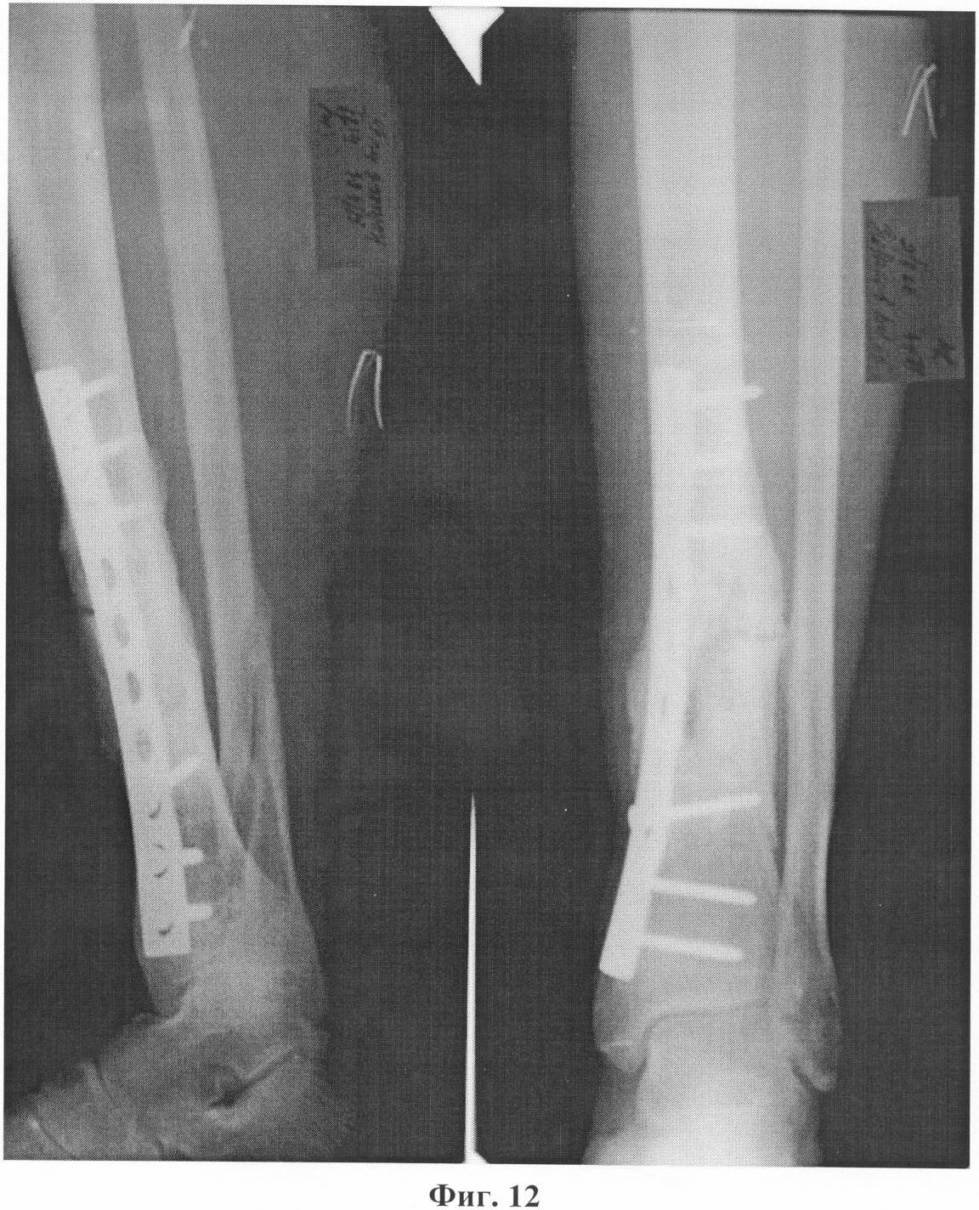

Фиг.9. Контрольная рентгенография после краевой кортикотомии, эндостальной декортикации, пластики интрамедуллярной полости коллостом и костной стружкой, накостного остеосинтеза пластиной со стимуляцией остеогенеза химотрипсином.

Больной Н., 55 лет, 23 июня 2005 года в результате бытовой травмы получил закрытый оскольчатый перелом обеих костей левой голени. Доставлен в городскую клиническую больницу г.Москвы, где был произведен остеосинтез большеберцовой кости левой голени пластиной АО с ограниченным контактом. Послеоперационный период протекал без осложнений. Проведено восстановительное лечение, включающее ходьбу с костылями с дозированной, постепенно увеличивающейся нагрузкой на оперированную конечность. Через 3 месяца после операции начал ходить с палочкой с полной нагрузкой на левую стопу. Однако при ходьбе отмечал умеренные боли в области перелома. Динамический рентгеноконтроль демонстрировал замедленную консолидацию перелома большеберцовой кости на фоне сросшегося перелома малоберцовой кости. В мае 2006 года боли в голени при ходьбе усилились. При контрольной рентгенографии обнаружен ложный сустав большеберцовой кости с переломом накостной металлоконструкции и миграцией винтов (фиг.8). 6 июня 2006 года под общим обезболиванием сломанная пластина была удалена с выполнением операции на ложном суставе по разработанному способу (фиг.9). После снятия швов и ликвидации отека произведена иммобилизация конечности укороченной циркулярной повязкой Scotchcast (до коленного сустава), и больной приступил к нагрузке в дозированном режиме. К концу 3-го месяца ходьба с полной нагрузкой без дополнительной опоры (фиг.10) в иммобилизирующей повязке (фиг.11), болей в голени нет, повязка снята, рентгенологически определяется сращение перелома большеберцовой кости (фиг.12). После проведения 2-х недельного реабилитационного курса функция конечности восстановлена в полном объеме (фиг.13, 14).